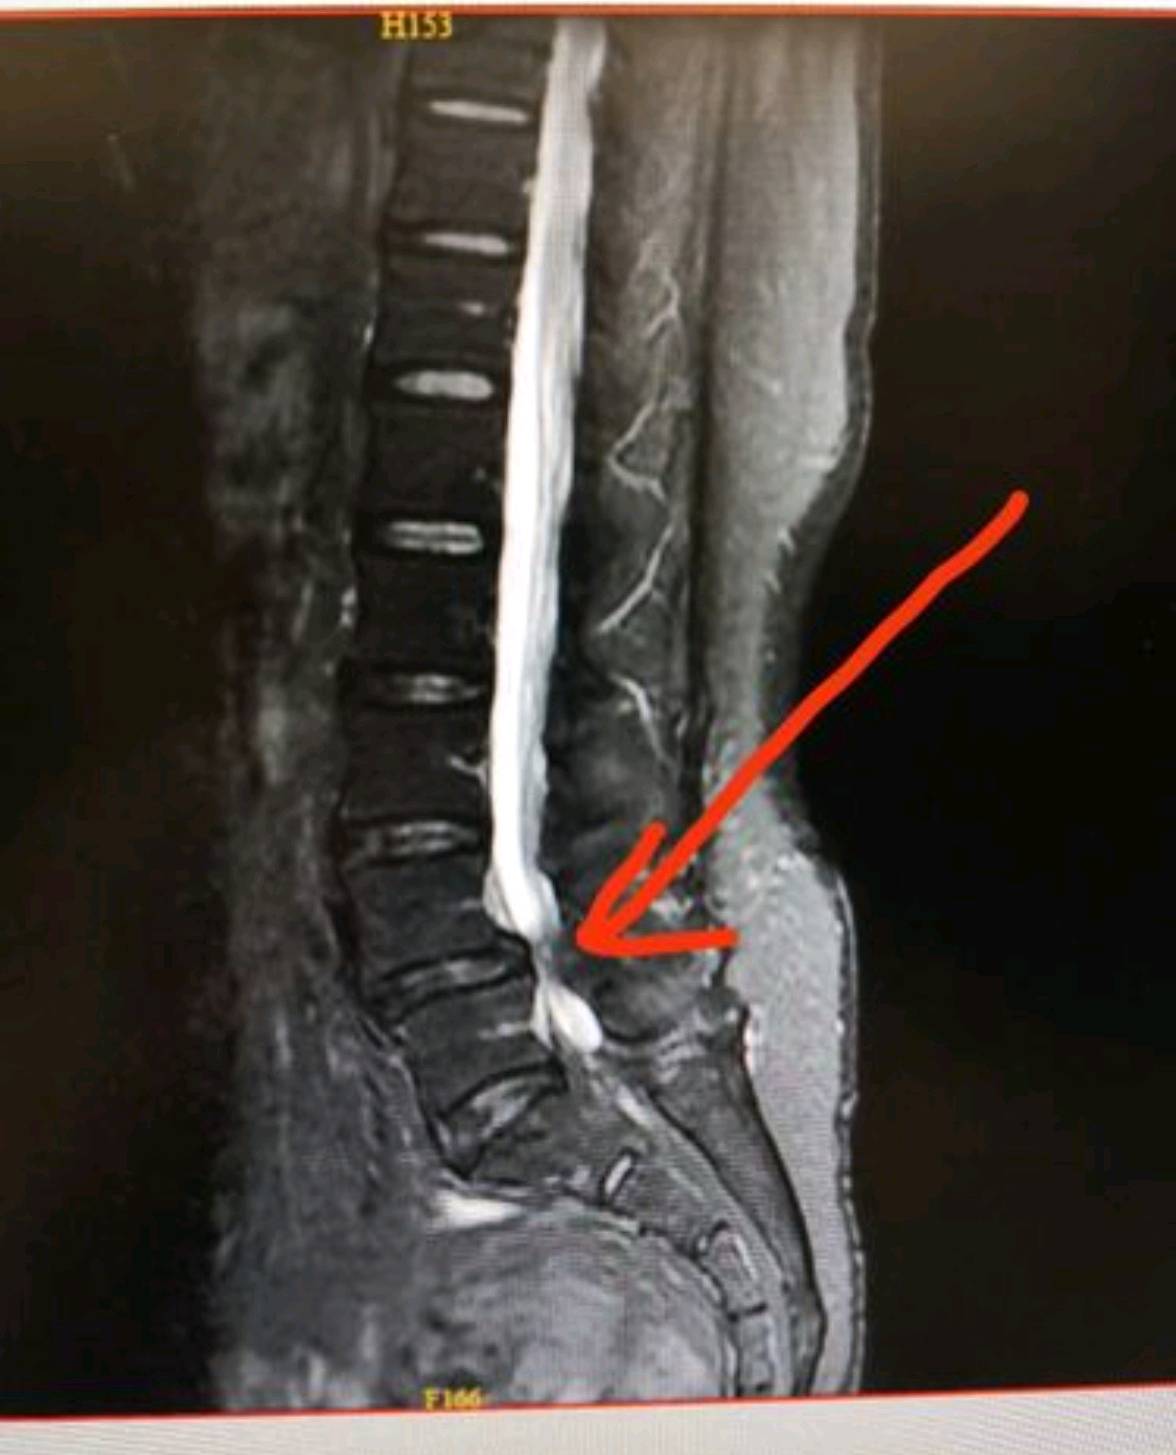

X线平片:可明确显示椎管矢状径较正常为狭小,其绝对值于15mm,甚至在12mm以下,个别病例不足10mm。

脊髓造影:显示典型“蜂腰状”缺损,根袖受压及阶段性狭窄等影像。